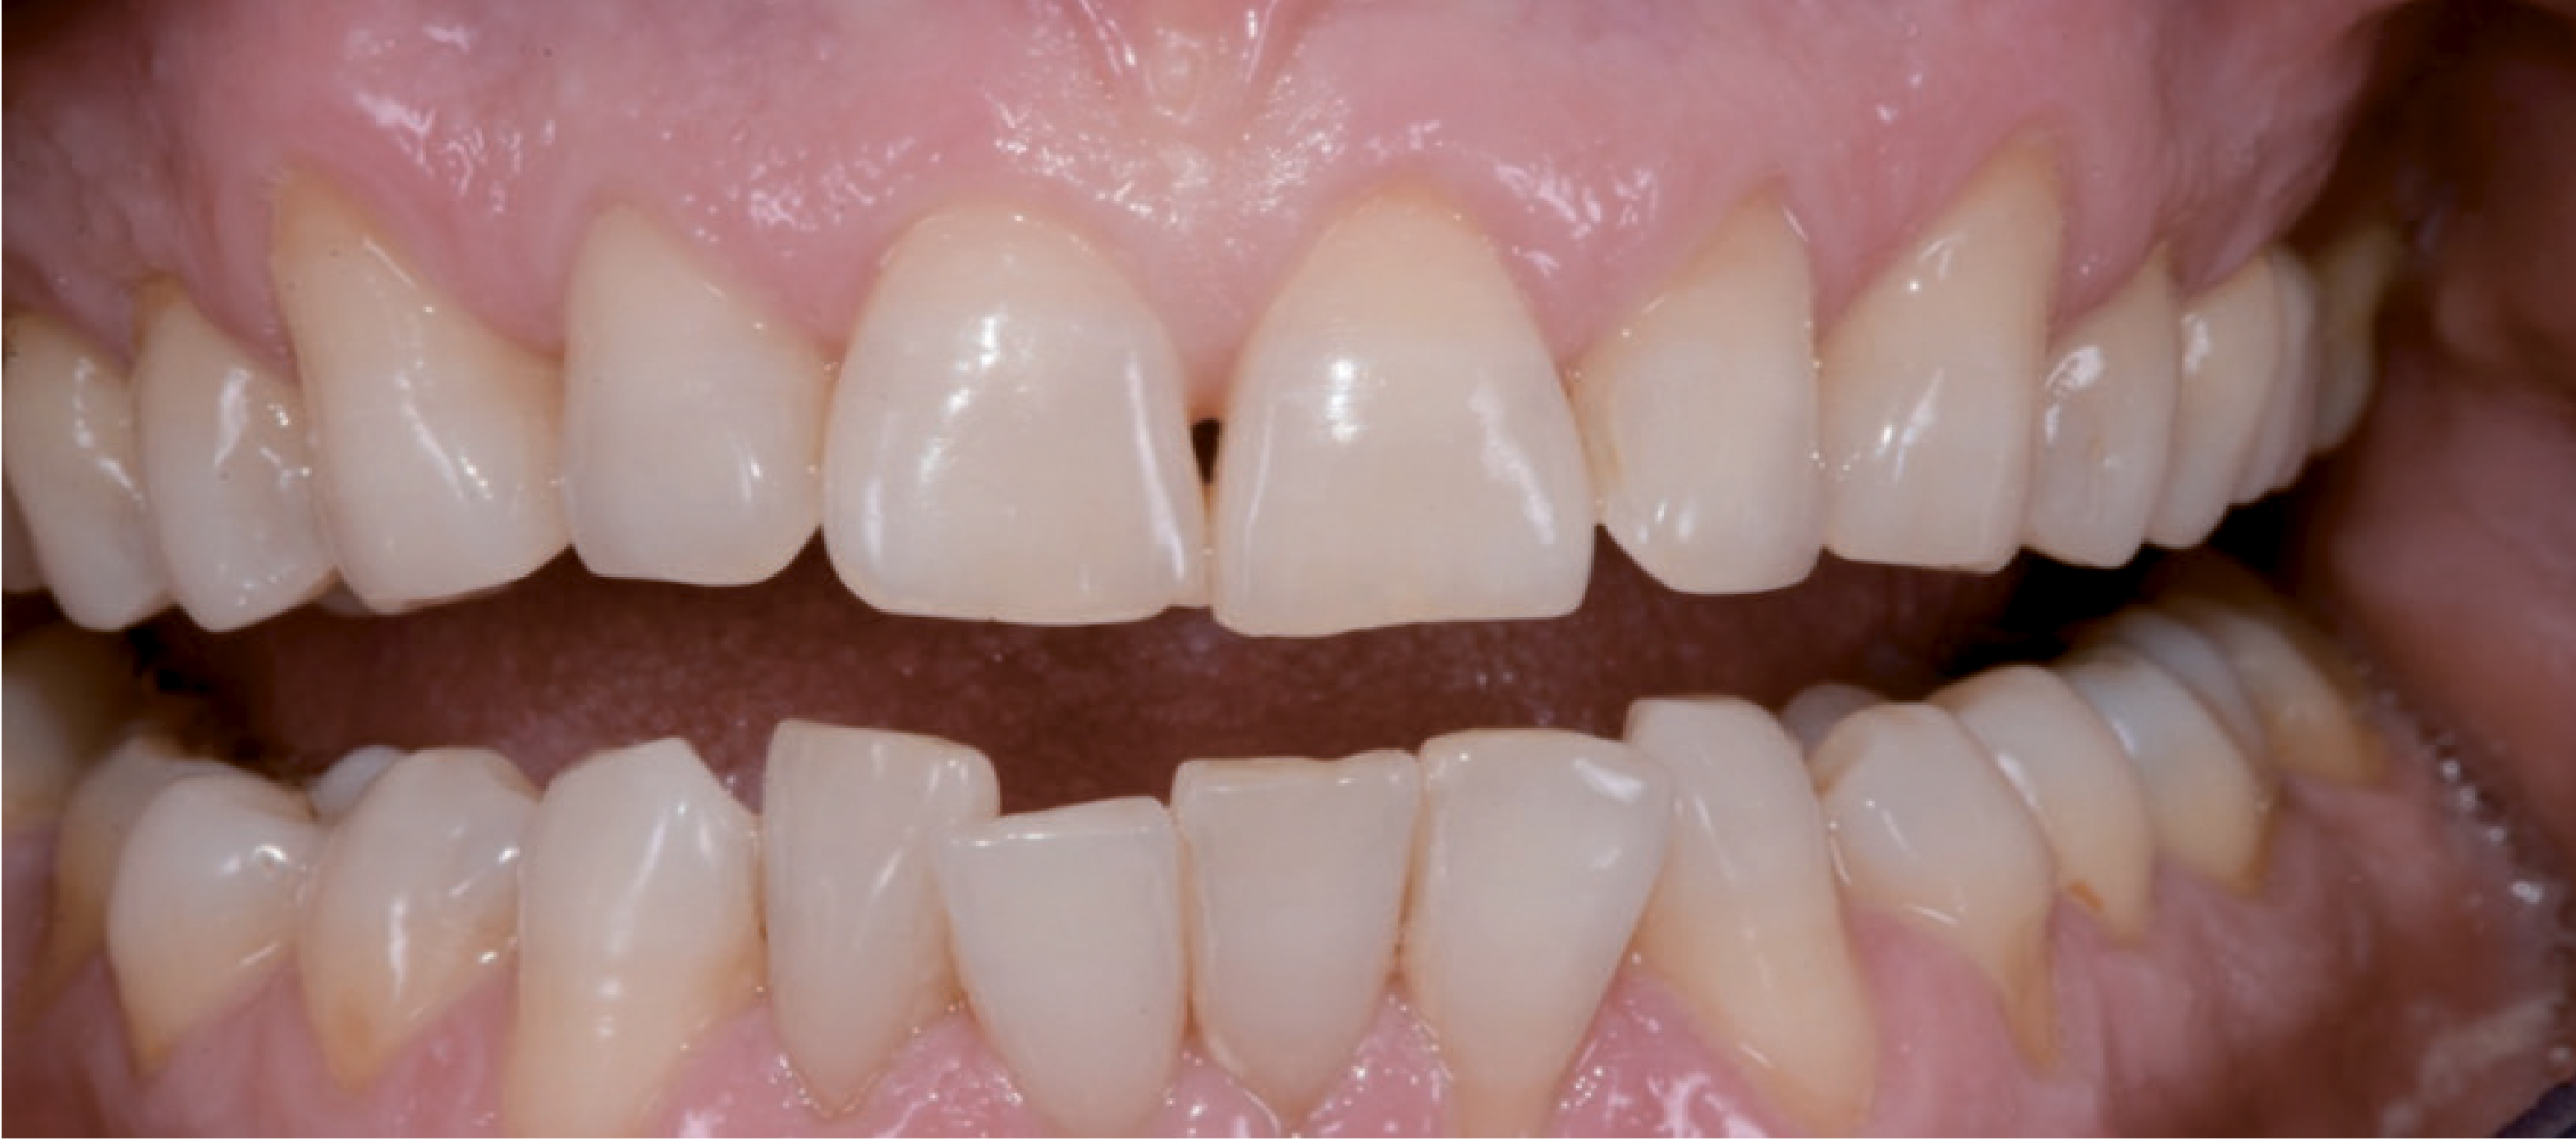

Так, верхній лівий центральний різець був подовжений, і на ньому були явні ознаки стирання. Крім того, ікла були стерті, і це призвело до відсутності фізіологічних орієнтирів. Через положення верхньої губи під час посмішки було видно рівний ясенний край і правильну середню лінію на верхній щелепі, тимчасом як зуби нижньої щелепи були розташовані дуже близько один до одного (мал. 3).

Множинні гінгівальной рецесії були присутні переважно в естетичній зоні, за винятком лівих верхніх різців. Центральні різці, тобто 11, 21 і 22, були вивернуті із зубної дуги. В області різців нижньої щелепи була скупченість, і загалом вони занадто помітно виступали, були нахилені та зміщені. Проблем функціонального характеру пацієнт не відчував. Розбіжностей між центральним мищелковим положенням і стандартною інтеркуспідацією не було. Водночас безперечно було потрібно ортодонтичне лікування нижніх зубів. Стосовно функціонування, стерті ріжучі краї іклів потрібно було відновити, щоб відтворити природний осьовий напрямок ікла.